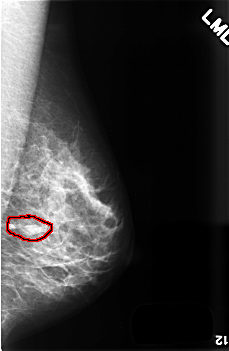

C_0507_1.RIGHT_MLO

FILE: C_0507_1.RIGHT_MLO.OVERLAY

TOTAL_ABNORMALITIES 1

ABNORMALITY 1

LESION_TYPE MASS SHAPE ROUND MARGINS CIRCUMSCRIBED

ASSESSMENT 3

SUBTLETY 3

PATHOLOGY BENIGN

TOTAL_OUTLINES 1

BOUNDARY